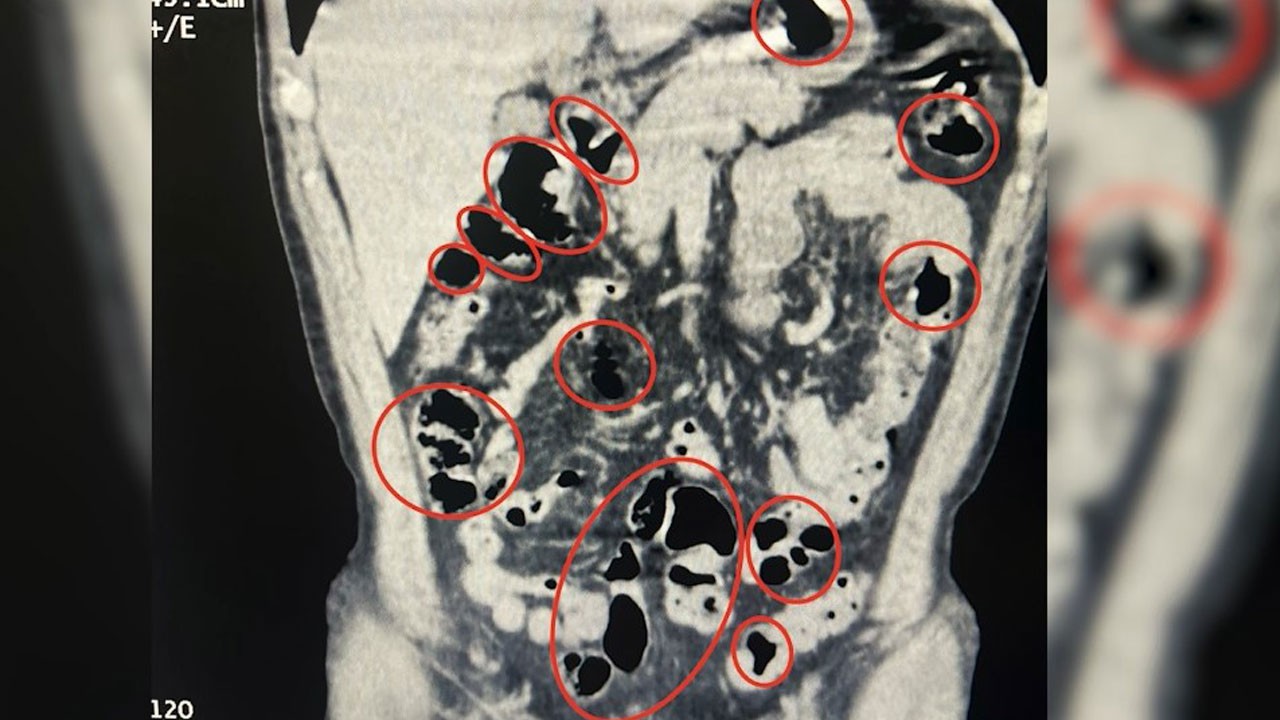

İl Emniyet Müdürlüğü Narkotik Suçlarla Mücadele Şube Müdürlüğü ile İstihbarat Şube Müdürlüğü ekiplerinin çalışması sonucu Tatvan ilçe girişinde durdurulan bir yolcu otobüsünde seyahat eden yabancı uyruklu 2 kişinin üzerinde arama yapıldı. Aramalarda şüphelilerin üzerinde 36 kapsül içerisinde uyuşturucu ele geçirildi. Tatvan Devlet Hastanesi’ne götürülen şüphelilerin burada yapılan röntgen ve tomografi incelemelerinde de mide ve bağırsaklarında yabancı cisimler tespit edildi. Tıbbi müdahale sonucu şüphelilerin yuttuğu 14 kapsül çıkarıldı. Toplam 50 kapsül halinde 385 gram metamfetamin ele geçirilen 2 şüpheli gözaltına alındı.